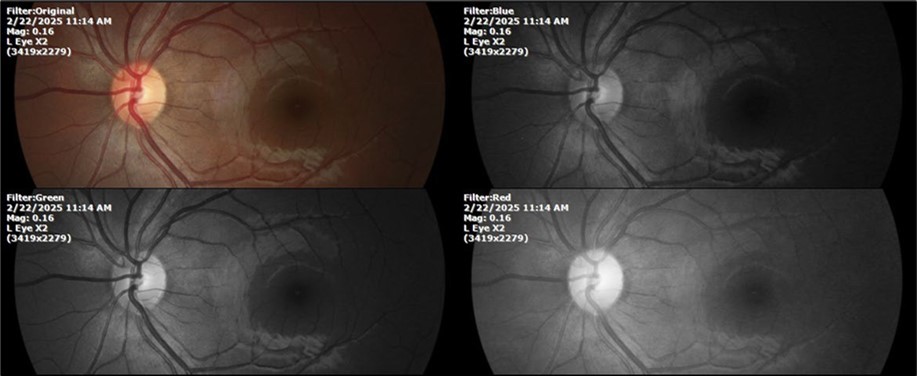

February 22, 2025

There is no pain, only minimal discomfort, and my vision has improved (Figure 20, Figure 21, Figure 22, Figure 23, Figure 24)

SpO2 %: 91 %

Heartbeat: 67 x´

Sciascopy: ++/++

Figure 20.The mirror reflection of the affected (right) eye continues to improve.

Figure 21.The anterior segment of the right eye responds with difficulty to mydriatics, which is usual in diseased eyes.

Figure 22.The whitish mass of phantom cells continues to decrease. The treatment continues to be based on ǪIAPI 1®, sublingual drops, three drops every hour, for as long as the patient is awake.

Figure 23.The mirror reflection of the left eye, without anomalies.

Figure 24.The eye that was not affected by the trauma (left side) remains in good condition.